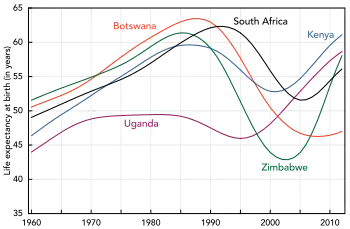

HIV/AIDS has become a chronic rather than an acutely fatal disease in many areas of the world.[205] Prognosis varies between people, and both the CD4 count and viral load are useful for predicted outcomes.[33] Without treatment, average survival time after infection with HIV is estimated to be 9 to 11 years, depending on the HIV subtype.[7] After the diagnosis of AIDS, if treatment is not available, survival ranges between 6 and 19 months.[206][207] ART and appropriate prevention of opportunistic infections reduces the death rate by 80%, and raises the life expectancy for a newly diagnosed young adult to 20–50 years.[205][208][209] This is between two thirds[208] and nearly that of the general population.[34][210] If treatment is started late in the infection, prognosis is not as good:[34] for example, if treatment is begun following the diagnosis of AIDS, life expectancy is ~10–40 years.[34][205] Half of infants born with HIV die before two years of age without treatment.[186][211]

The primary causes of death from HIV/AIDS are opportunistic infections and cancer, both of which are frequently the result of the progressive failure of the immune system.[189][212] Risk of cancer appears to increase once the CD4 count is below 500/μL.[34] The rate of clinical disease progression varies widely between individuals and has been shown to be affected by a number of factors such as a person's susceptibility and immune function;[213] their access to health care, the presence of co-infections;[206][214] and the particular strain (or strains) of the virus involved.[215][216]

A small group of individuals continue to dispute the connection between HIV and AIDS,[308] the existence of HIV itself, or the validity of HIV testing and treatment methods.[309][310] These claims, known as AIDS denialism, have been examined and rejected by the scientific community.[311] However, they have had a significant political impact, particularly in South Africa, where the government's official embrace of AIDS denialism (1999–2005) was responsible for its ineffective response to that country's AIDS epidemic, and has been blamed for hundreds of thousands of avoidable deaths and HIV infections.[312][313][314]